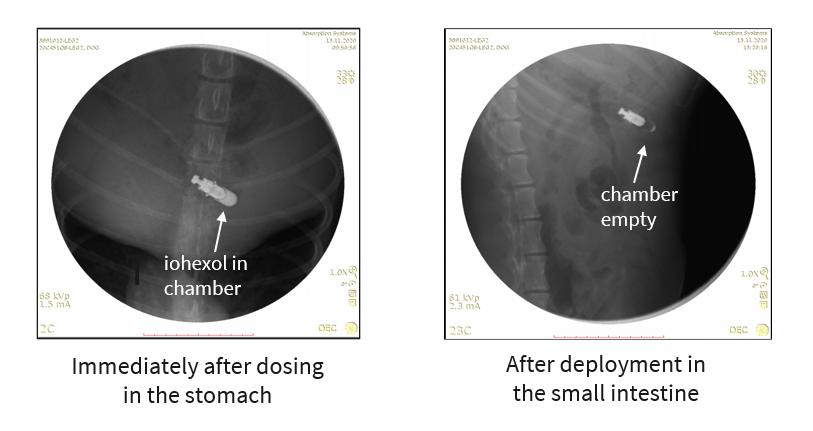

We conducted a preclinical study with an autonomous BIOJET device delivered orally to canines. The study was a single-dose study evaluating safety and tolerability of the device in addition to the ability of the device to activate and deliver payload when it reached the small intestine. We evaluated device function by loading the device with a contrast agent (iohexal) and sequentially imaged

9

post-administration as the device transited through the body. The images below are taken from the study and show the contrast agent inside the capsule in the stomach and after deployment in the small intestine.

img188384320_6.jpg

This study demonstrated that the device can reliably deploy in the small intestine, which supports oral administration of the BIOJET device. We are continuing to advance development of the BIOJET platform through preclinical testing.